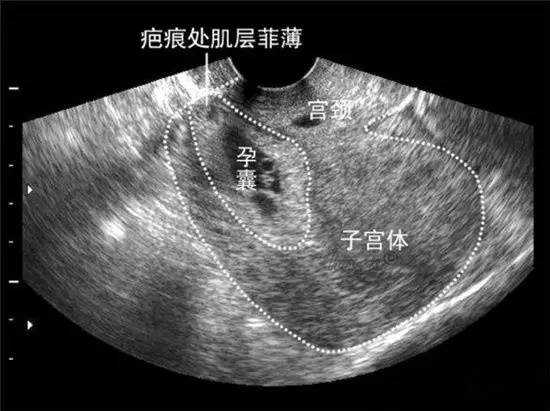

(2)子宫瘢痕破裂:造成子宫瘢痕的原因主要有剖宫产术,子宫肌瘤剥除术,子宫破裂或穿孔修补术,子宫畸形矫形术等;造成破裂的原因是妊娠子宫的机械性牵拉导致瘢痕处破裂或者子宫瘢痕处内膜受损,胎盘植入,穿透性胎盘导致子宫自发破裂。近些年剖宫产术迅速增加子宫体部纵切口剖宫产再次妊娠容易并发子宫破裂,分析原因除宫体部纵切口和下段横切口解剖性质不同外,还要考虑感染因素的作用,因为目前采用子宫体部纵切口剖宫产的患者通常经过了漫长的产程,多次阴道检查,感染几率增加。